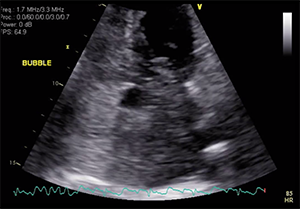

Transthoracic echocardiography (TTE) with bubble echocardiography revealed a large right-to-left shunt at rest, possibly via a patent foramen ovale (PFO). Transesophageal echocardiography (TEE) was deemed risky due to the patient’s borderline respiratory status and large PE. The results of brain CT were negative for stroke. Laboratory workup identified a new diagnosis of factor V Leiden deficiency. The patient’s primary oncologist predicted a high probability of curing her B-cell lymphoma with chemotherapy. The patient was considered very high risk for open embolectomy, right atrial clot removal, and PFO closure by a cardiothoracic surgeon; thus, the structural team was consulted for percutaneous closure of the PFO to prevent further paradoxical embolization.

Given the active paradoxical embolization, the decision was made to perform PFO closure initially. This was successfully achieved with a 30-mm Cardioform device guided by intracardiac echocardiography without complications. The patient underwent a staged extraction of the right atrial mass with an AngioVac cannula 72 hours later. Pathologic examination of the extracted mass revealed predominantly thrombus without evidence of tumor (Figure 2). I agree with the panelists that a more aggressive approach to the PE could have been taken. However, concerns were raised about the use of tissue plasminogen activator (albeit locally) given the fresh femoral cutdown sites that were used to perform the aortoiliac thrombectomy.